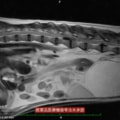

■ MRI検査

第5-6腰椎間で右側神経根が腫大し、脊柱管内に連続した腫瘤病変が認められました。脊髄および馬尾神経は右側から重度に圧迫されていました。

MRI検査所見

MRI 1

MRI 2